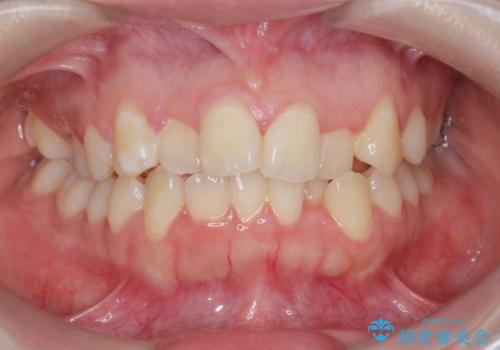

[マウスピース矯正] がたがたの歯並びをきれいにしたい

![[マウスピース矯正] がたがたの歯並びをきれいにしたいの症例 治療前](https://seimitsushinbi.jp/wp/wp-content/uploads/2025/06/0d238550c8a0fddc4de7b2c337c6c786-500x350.jpg?v=1750323380)

![[マウスピース矯正] がたがたの歯並びをきれいにしたいの症例 治療後](https://seimitsushinbi.jp/wp/wp-content/uploads/2025/06/IMG_0002-2-500x350.jpg?v=1750323305)